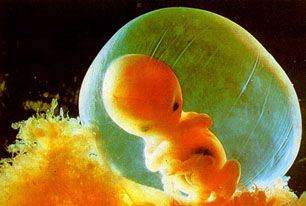

ชีวิตของคนเรานั้นจะเริ่มต้นก่อตัวอยู่ภายในโพรงมดลูกของแม่และจะเจริญเติบโตขึ้นทีละน้อย ๆ โดยอาศัยอาหารที่มาจากเลือดของแม่ทางสายสะดือเด็กจะค่อยเจริญเติบโตขึ้นเรื่อย ๆ ในท้องของแม่จนครบ 9 เดือน จึงจะเจริญเติมที่และคลอดออกมาเป็นทารกตัวเล็ก ๆ น่ารัก

มีแม่บางคนที่ตั้งครรภ์ไม่ทันถึง 7 เดือน ก็มีเหตุบังเอิญหรือเหตุจำเป็นต้องคลอดลูกออกมาเสียก่อนเราเรียกการคลอดเด็กที่อยู่ในท้องไม่ทันถึง 7 เดือน แล้วถูกขับออกมาเช่นนี้ว่า "แท้งลูก" ลูกที่แท้งมักมีลักษณะไม่แข็งแรง ไม่สมบูรณ์ตัวเล็กมากอวัยวะสำคัญ เช่น ปอดยังทำงานไม่ได้ ดังนั้นเมื่อเด็กแท้งออกมาก็จะตาย

การตั้งครรภ์ของแม่บางคนอาจไม่ราบรื่นนักเป็นต้นว่าแม่มีโรคภัยไข้เจ็บประจำตัวอยู่นานเป็นผลให้เด็กในท้องเจริญเติบโตไม่ได้จึงแท้งออกมาหรืออาจเป็นเพราะลูกในท้องที่ก่อตัวอ่อน ๆ อยู่นั้นมีความพิการธรรมชาติจึงขับเด็กออกมาจากท้องของแม่ทั้ง ๆ ที่ยังอยู่ในท้องไม่ทันถึง 7 เดือน อย่างนี้เรียกว่า "การแท้งลูก" และเด็กที่เกิดจากการแท้งก็จะตายเพราะเหตุว่าอวัยวะต่าง ๆ ยังไม่เจริญเต็มที่การแท้งเองโดยธรรมชาติเช่นนี้เกิดขึ้นไม่บ่อยนัก ในแม่ที่ตั้งครรภ์ 10 ราย อาจมีการแท้งเอง 1 รายเท่านั้น